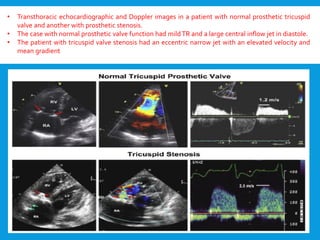

• Transthoracic echocardiographic and Doppler images in a patient with normal prosthetic tricuspid

valve and another with prosthetic stenosis.

• The case with normal prosthetic valve function had mildTR and a large central inflow jet in diastole.

• The patient with tricuspid valve stenosis had an eccentric narrow jet with an elevated velocity and

mean gradient